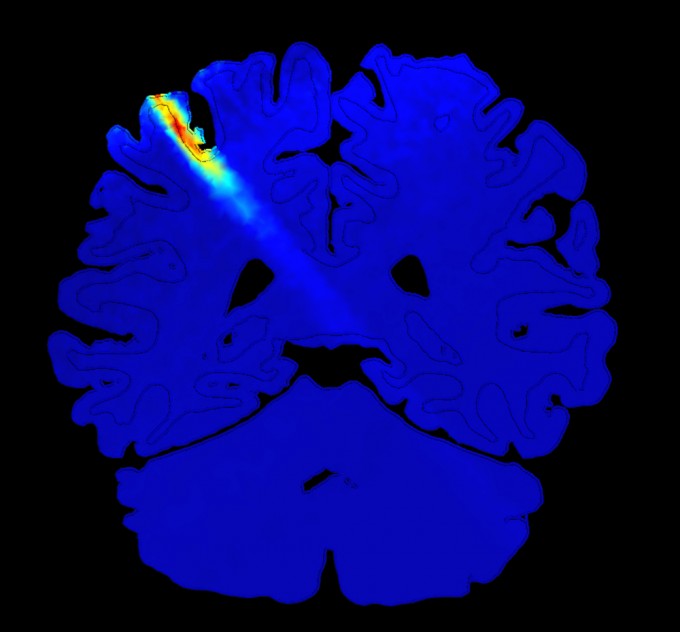

Ultrasound directed to the human brain can boost spatial resolution

Whales, bats, and even praying mantises also use ultrasound as a sensory guidance system